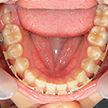

13. 術後下顎

前歯部の叢生および左下2,3番間の乱杭が改善され、全ての歯牙の唇面の連続性が確保されています。当然、口腔清掃しやすい環境になりますし、発音などにも良い影響を与えます。またこれから年齢を重ねても、虫歯や歯周病の予防に繋がります。